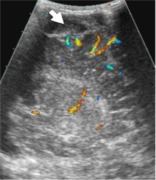

НСГ, при которой обнаружено резкое смещение срединных структур головного мозга справа

налево, расширение субдурального пространства справа и расширение фрагментов левого

бокового желудочка. При проведении дуплексного допплеровского сканирования выявлено

резко обеднение церебрального сосудистого рисунка (больше - справа), при допплерографии

определялось резкое повышение показателей периферического сопротивления артериального

кровотока в бассейнах передних и средних мозговых артерий с обеих сторон (рис. 3).

Рисунок 3. Ребенок Х., осмотр в день

поступления.

| а - нейросонография, В-режим, фронтальная плоскость. Определяется значительное

расширение субдурального пространства справа (белая стрелка), выраженное смещение

срединных структур мозга справа налево, передний рог бокового желудочка справа

компрессирован, слева - дилятирован до 8мм |

б - то же, фрагмент |

в - тот же ребенок, сагиттальная плоскость, фрагмент. Определяется

значительное расширение субдурального пространства справа (белая стрелка), дифференцируется

арахноидальная оболочка (треугольная стрелка) и субарахноидальное пространство

(контурная треугольная стрелка) |

г - тот же ребенок, сагиттальная плоскость, дуплексное допплеровское

сканирование. Зна-чительное обеднение церебрального сосудистого рисунка, Расширение

субдурального пространства (белая стрелка) |

д - тот же ребенок, допплерография на средней мозговой артерии справа. Резкое

повышение показателей периферического сопротивления (RI = 1,0) с исчезновением

диастолического артериального компонента |